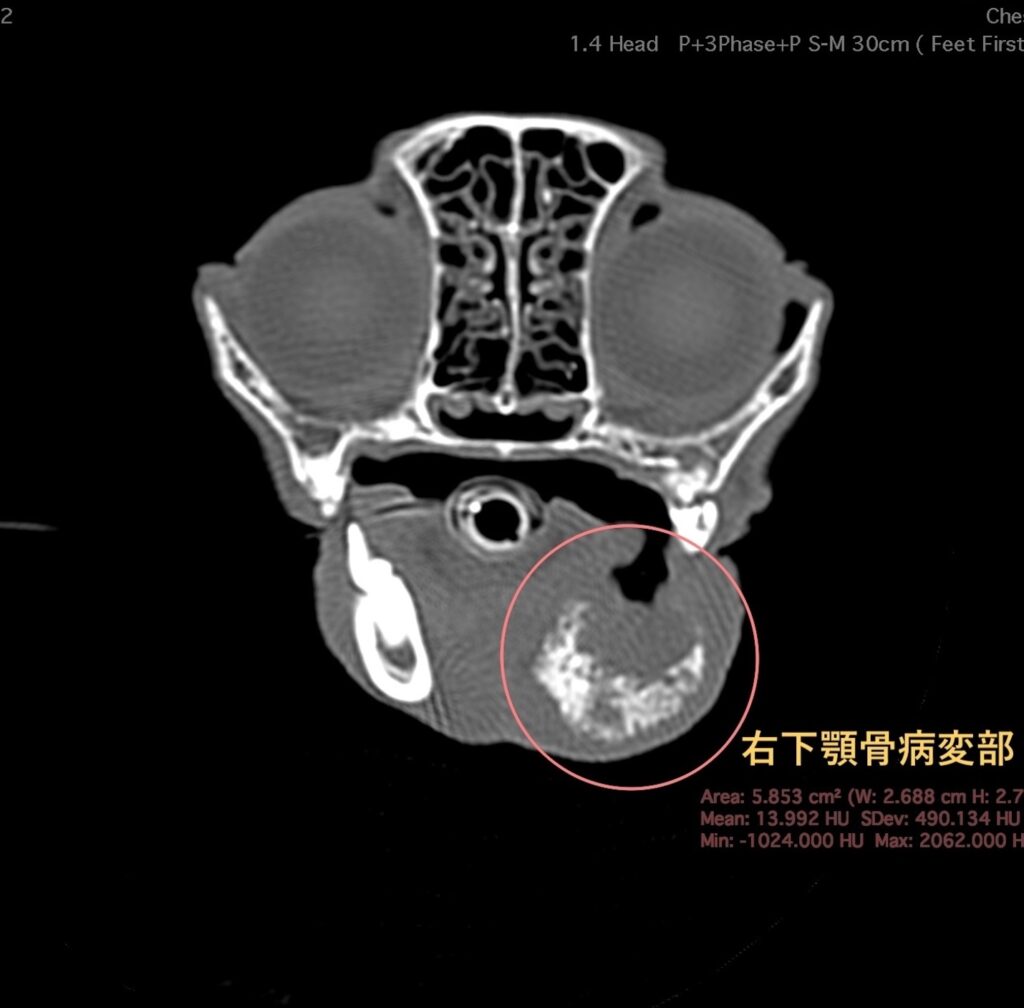

臨床経過と診察時の所見から下顎の腫瘍を疑い、2日後に全身麻酔下でのCT検査を行う。

CT検査で右下顎骨の骨融解、骨増生を認める。